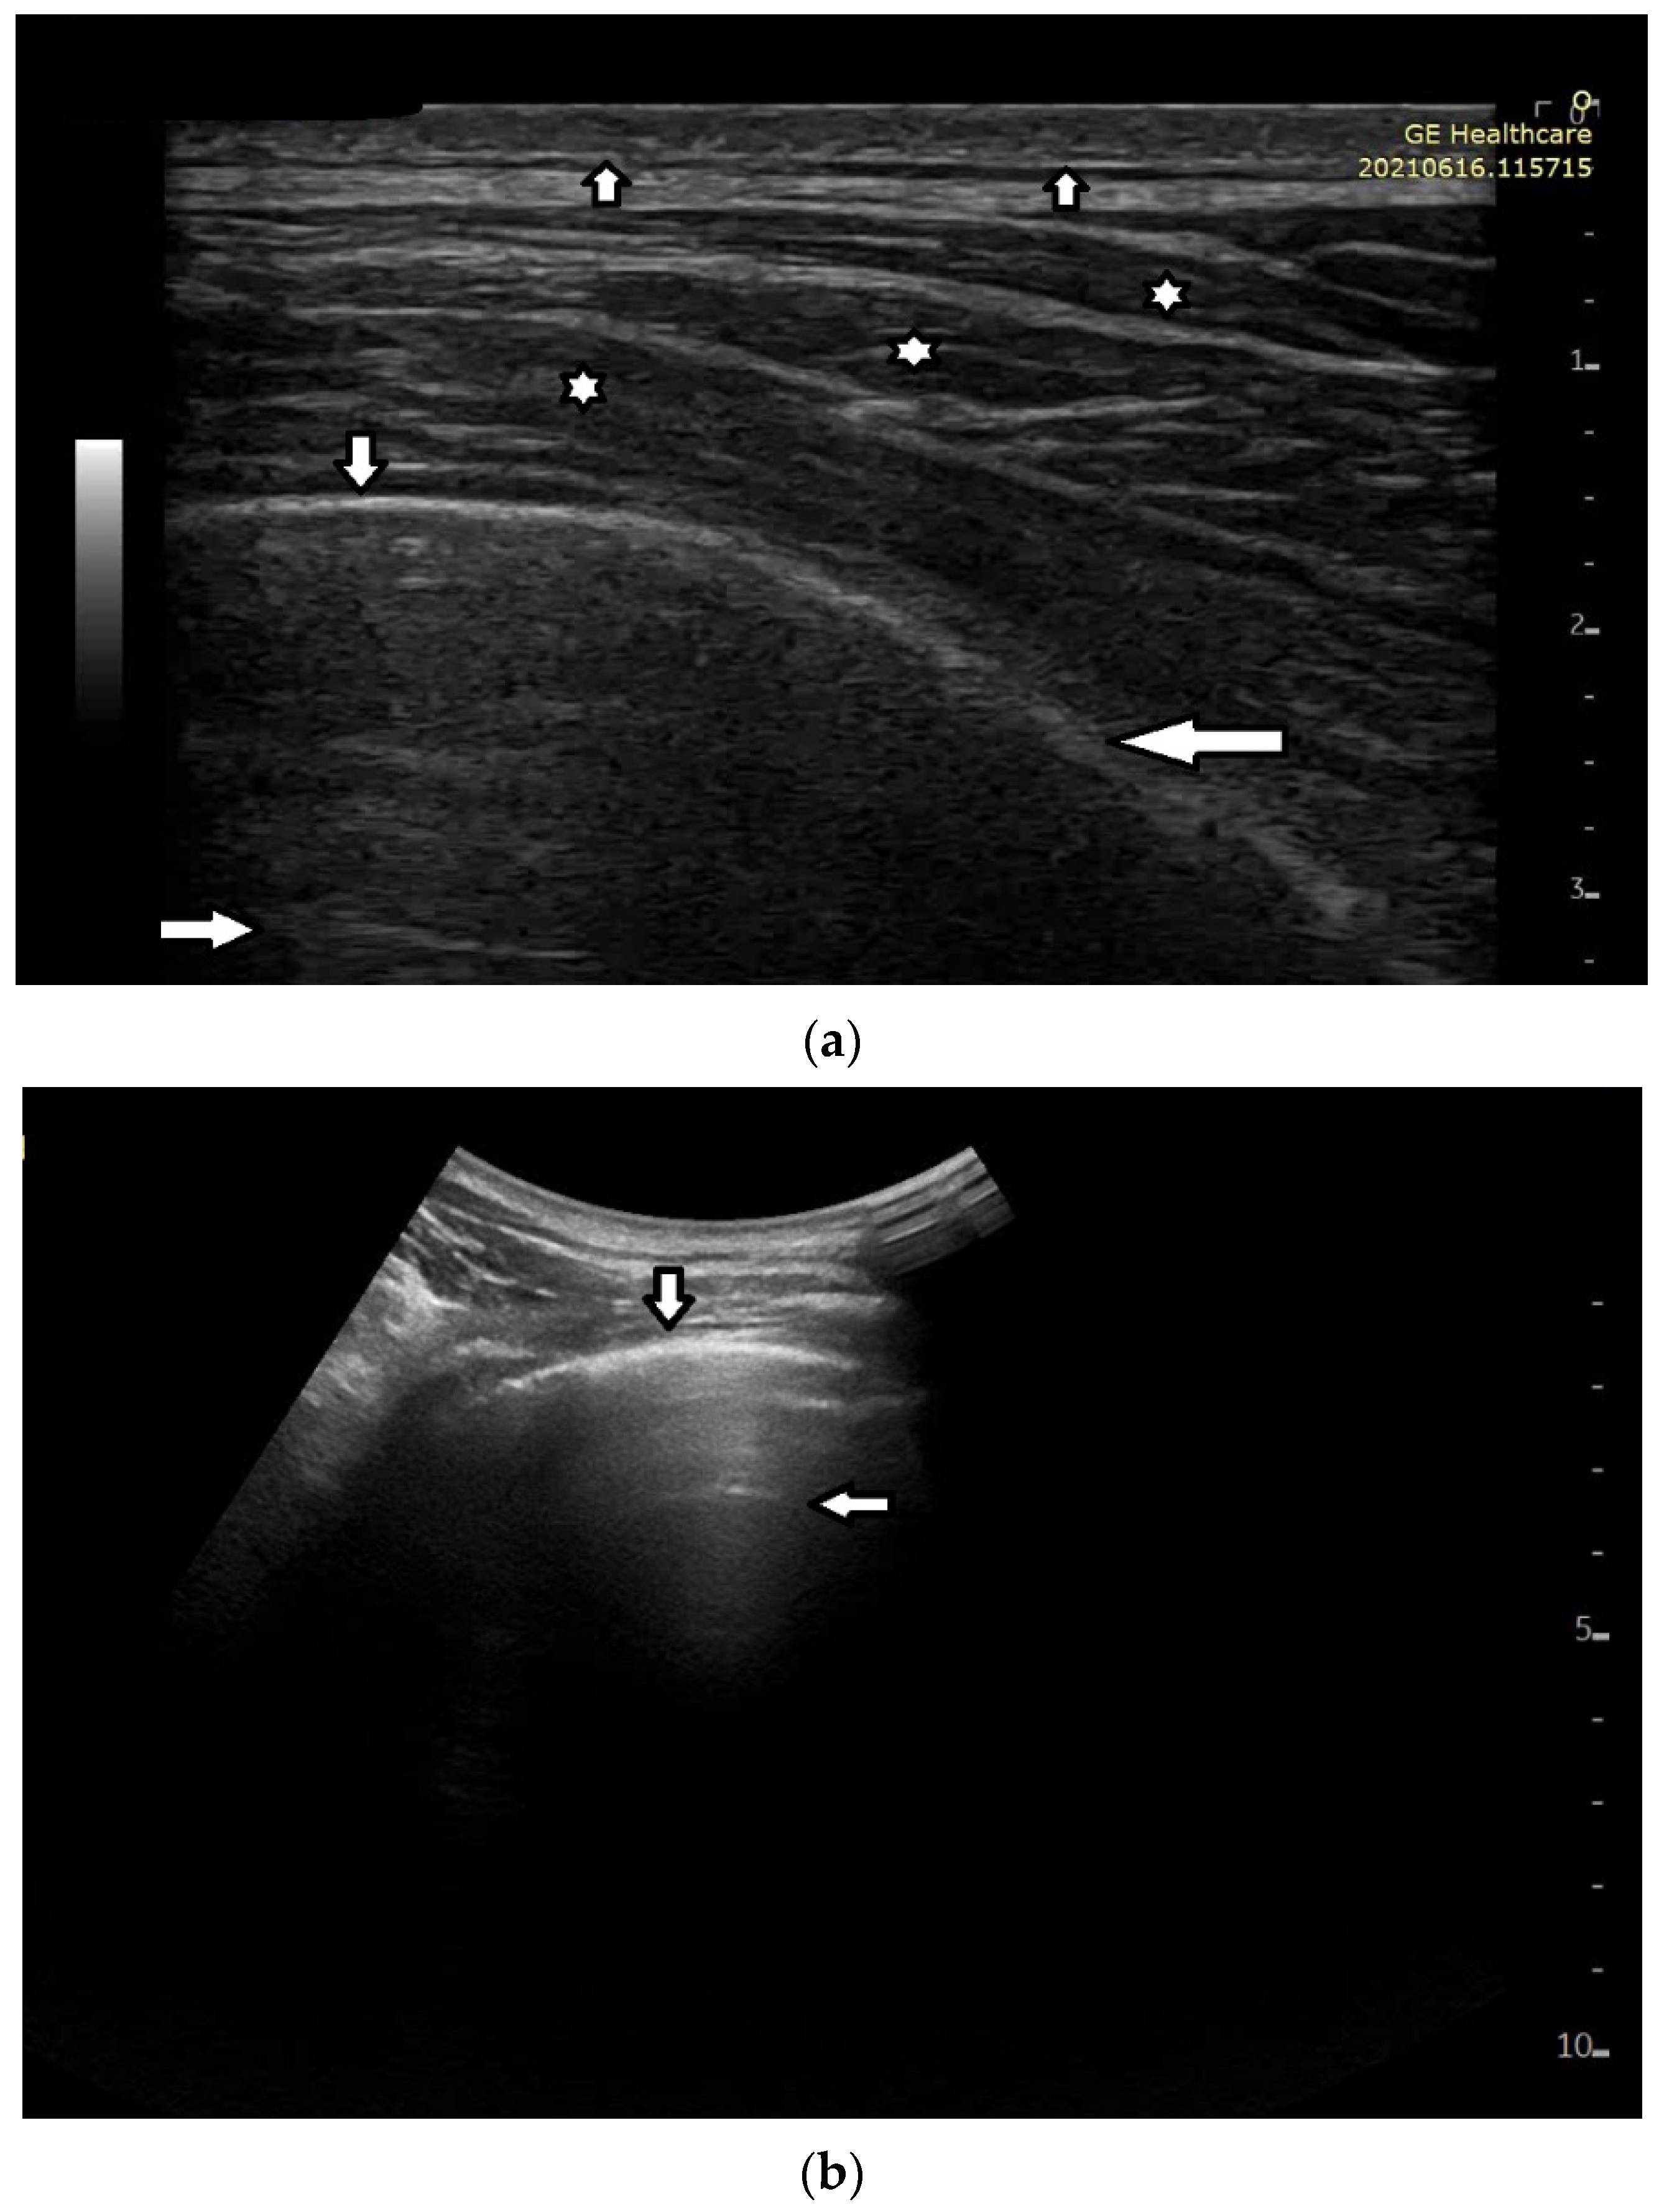

Based on clinical observations, we know that in pulmonary fibrosis, B lines often reduce their length when higher frequencies are used on a convex probe (from 2 MHz up to 6 MHz) (see Figure 4a,b). In the case of cardiac edema, the length of a B line is often stable, irrespective of the frequency modification (see Figure 4c,d) [3]. Why does the length of B lines sometimes change when varying the pulse central frequency, whereas sometimes the length does not significantly change?

Look at the entire image, and you will find the answer. When using the 2 MHz frequency, the image (Figure 4a) is brighter everywhere: the thoracic wall is brighter; the pleura line is brighter; the two lateral sides of the image (where there are no artifacts) are brighter, and the artifacts themselves are brighter. In my opinion, the problem is primarily given by the attenuation, which increases when increasing the frequency. In order to compensate such an effect, you should change the TGC. As a rule of thumb, you can consider an attenuation coefficient of 1 db/cm/Mhz. When varying the frequency from 2 MHz to 6 MHz, you are introducing an additional attenuation of 4db per centimeter. From a practical point of view, when using the 6 MHz frequency, the probe receives a signal from the depth of half a centimeter, whose amplitude is less than half the amplitude of the signal it would receive from the same depth if a 2 MHz pulse were used. Moreover, it is worth noting that the ratio between the amplitudes of the two temporal signals s6(t) and s2(t) (the echoes received by the probe) decreases exponentially when the delay t increases.

The answer is a bit more complex when cardiac edema is considered. In the case of fibrosis, larger acoustic traps and wider linking channels are, in general, expected that reradiate almost the entire power spectrum of the trapped acoustic pulse. In this case, attenuation is probably the main factor that influences the artifact length when varying the frequency. Therefore, the artifact length decreases when increasing the pulse central frequency since attenuation increases when increasing the frequency. On the contrary, in the case of cardiac edema, smaller acoustic traps and narrower linking channels are expected at the early stages of the pathology. Smaller traps can reradiate only a few harmonics, and the overlapping between the pulse spectrum and the spectral signature of the trap affects the artifact length much more than the attenuation factor. In these cases, the trap response to pulses with different frequencies is unpredictable.

Figure 4. (a) Pulmonary fibrosis in the course of interstitial lung disease: down arrows—pleural line; left arrows—B line artifact observed at 2 MHz frequency. (b) Pulmonary fibrosis in the course of interstitial lung disease: down arrows—pleural line; left arrows—vertical artifacts observed at 6 MHz frequency. The image was obtained from the same patient and identical assessment site as in Figure 4a. (c) Cardiac edema: down arrows—pleural line; left arrows—B-line artifacts observed at 2 MHz frequency. (d) Cardiac edema: down arrows—pleural line; left arrows—B-line artifacts observed at 6 MHz frequency. The image was obtained from the same patient and identical assessment site as in Figure 4c.